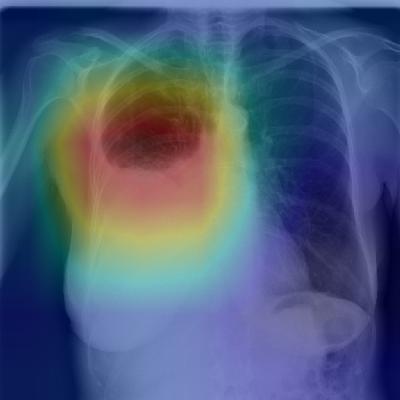

(c) Patient with primary lung malignancy and two large masses, one in the left lower lobe and one in the right upper lobe adjacent to the mediastinum. The model correctly identifies both masses in the X-ray.

Figure 2: CheXNet localizes pathologies it identifies using Class Activation Maps, which highlight the areas of the X-ray that are most important for making a particular pathology classification. The captions for each image are provided by one of the practicing radiologists.

Figure 2 shows several examples of CAMs on the pneumonia detection task as well as the 14-class pathology classification task.